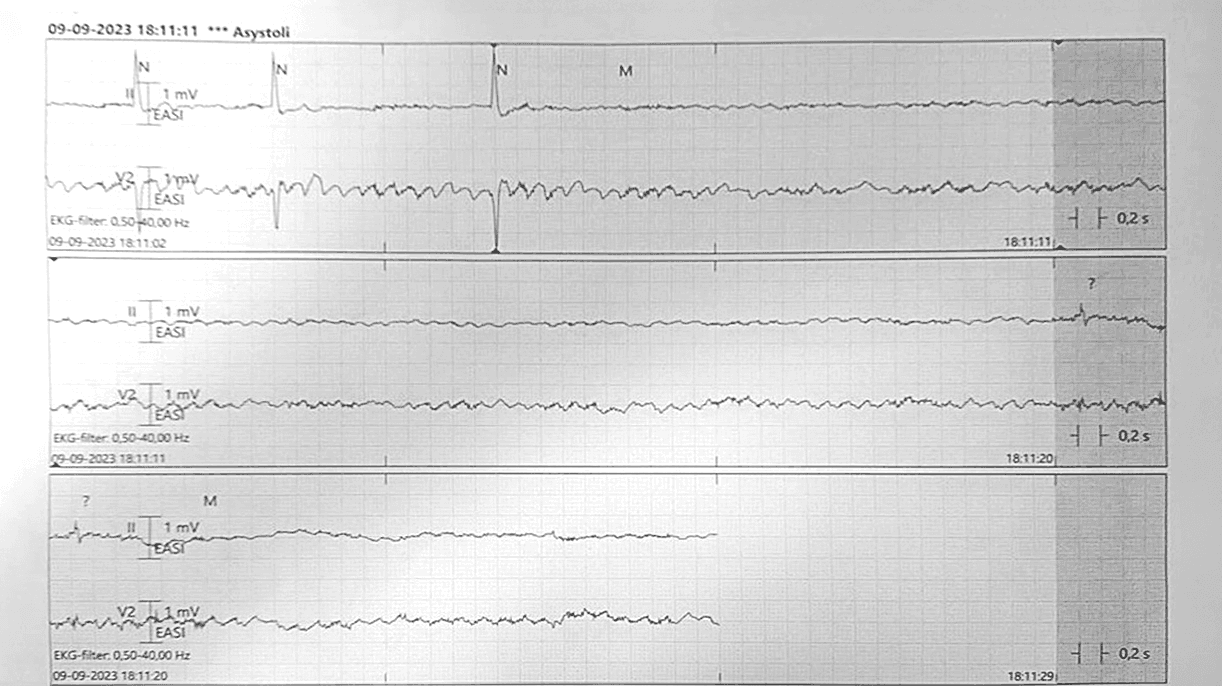

En 68-årig kvinde med permanent atrieflimren (AF) og mesial temporallapsepilepsi med hippokampal sklerose påvist ved MR-skanning af cerebrum blev indlagt efter krampeanfald. Patientens historik var domineret af fokale anfald med fjernhed. Kort efter indlæggelse fik hun yderligere tre selvlimiterende anfald. Ved personalets ankomst lå patienten på gulvet med generaliseret øget tonus og bevidsthedstab med åbne øjne. På telemetri sås under to af anfaldene > 30 sekunders asystoli (Figur 1). Patienten havde normalt kaliumniveau, ingen tegn på infektion og var ikke i frekvens-/rytmeregulerende, medicinsk behandling. Hun blev akut overflyttet med henblik på anlæggelse af temporært pacemakersystem. Lige før proceduren fik hun endnu et anfald på lejet under overvågning af hjerterytme. Ved ictus sås AF, men efter 30 sekunders krampeanfald fik patienten asystoli gennem 30 sekunder. Krampeanfaldet selvlimiterede efter i alt et minut, hvorefter patienten fik egenrytme og havde en kort postiktal fase, og det temporære pacemakersystem kunne anlægges. Under indlæggelsen blev det temporære pacemakersystem nedjusteret til basisfrekvens 40/minut med henblik på vurdering af permanent pacemakerbehov, og der blev foretaget ekkokardiografi, der var normal. Grundet perioder med højfrekvent AF blev der opstartet frekvenslimiterende behandling medførende pauser på 7-10 sekunder. Patienten fik derfor anlagt permanent enkeltkammerpacemaker på indikationen AF med pauser sekundært til nødvendig, frekvenslimiterende behandling. Under indlæggelsen blev konstateret for lavt plasmaniveau af antiepileptisk behandling, formodentlig på grund af nedsat komplians, hvorfor man overgik til dosisdispenseret medicin.